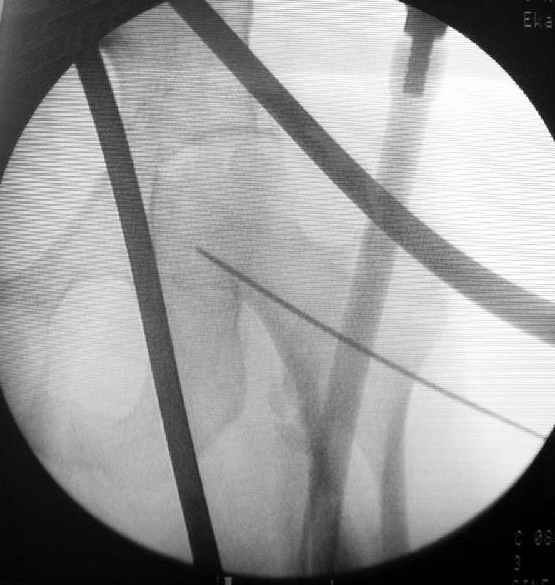

Как раз недавно у меня был примерный случай: больному 36 лет, поступил ночью, травма в результате мотоциклетной аварии, кроме чрезвертельного и спирального перелома левого бедра имеется переломы костей предплечья с этой же стороны. Скелетное вытяжение, а на следующий день больной про оперирован на ортопедическом столе с дистракцией. Чтобы не расколоть чрезвертельный перелом провели временную спицу ближе к переднему кортексу, из малого разреза костодержатель для репозиции, а фиксацию провели антиградным штифтом. Этапы операции на снимках.

Джолдас Кульджанов

Второй случай тоже репозиция из малого доступа, больному 19 лет, множественные огнестрельные повреждениия конечностей, живота и черепа, правая конечность холодная, без пульсации. Ортопедический диагноз: огнестрельный перелом правого бедра. При срочной ангиографии повреждения сосудов не подтвердилось, конечность из-за ургентности состояния больного зафиксирована временным наружным фиксатором и больной оставлен на операционном столе для срочной лапаротомии хирургической службой.

Больной долго оставался нестабильным, только на 14 день удалось заменить на антеградный интромедуллярный штифт TFN (trochanteric femoral nail) SmithNephew. После неудачной попытки закрытой репозиции, несмотря на использование "joystick", проксимальный стержень от

наружного фиксатора, (перелом начал срастаться) репозицию провели из малого доступа, затем остальные этапы операции.